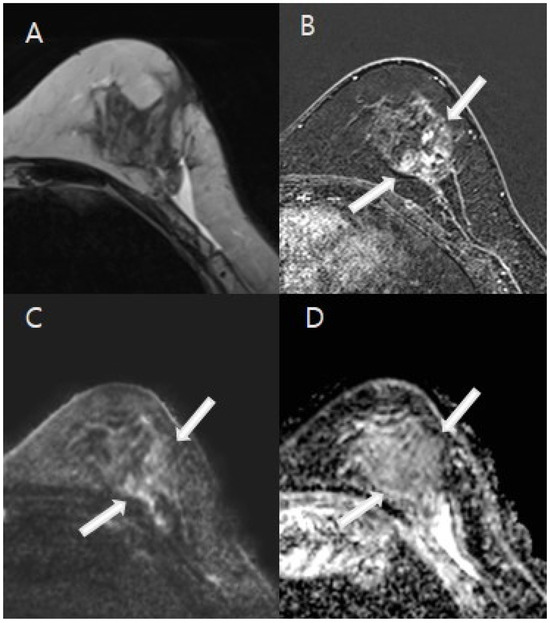

2.5. Mammography/Ultrasound Interpretation

3.2. Image Analysis Results

3.3. The Diagnostic Performance of the Imaging Modalities